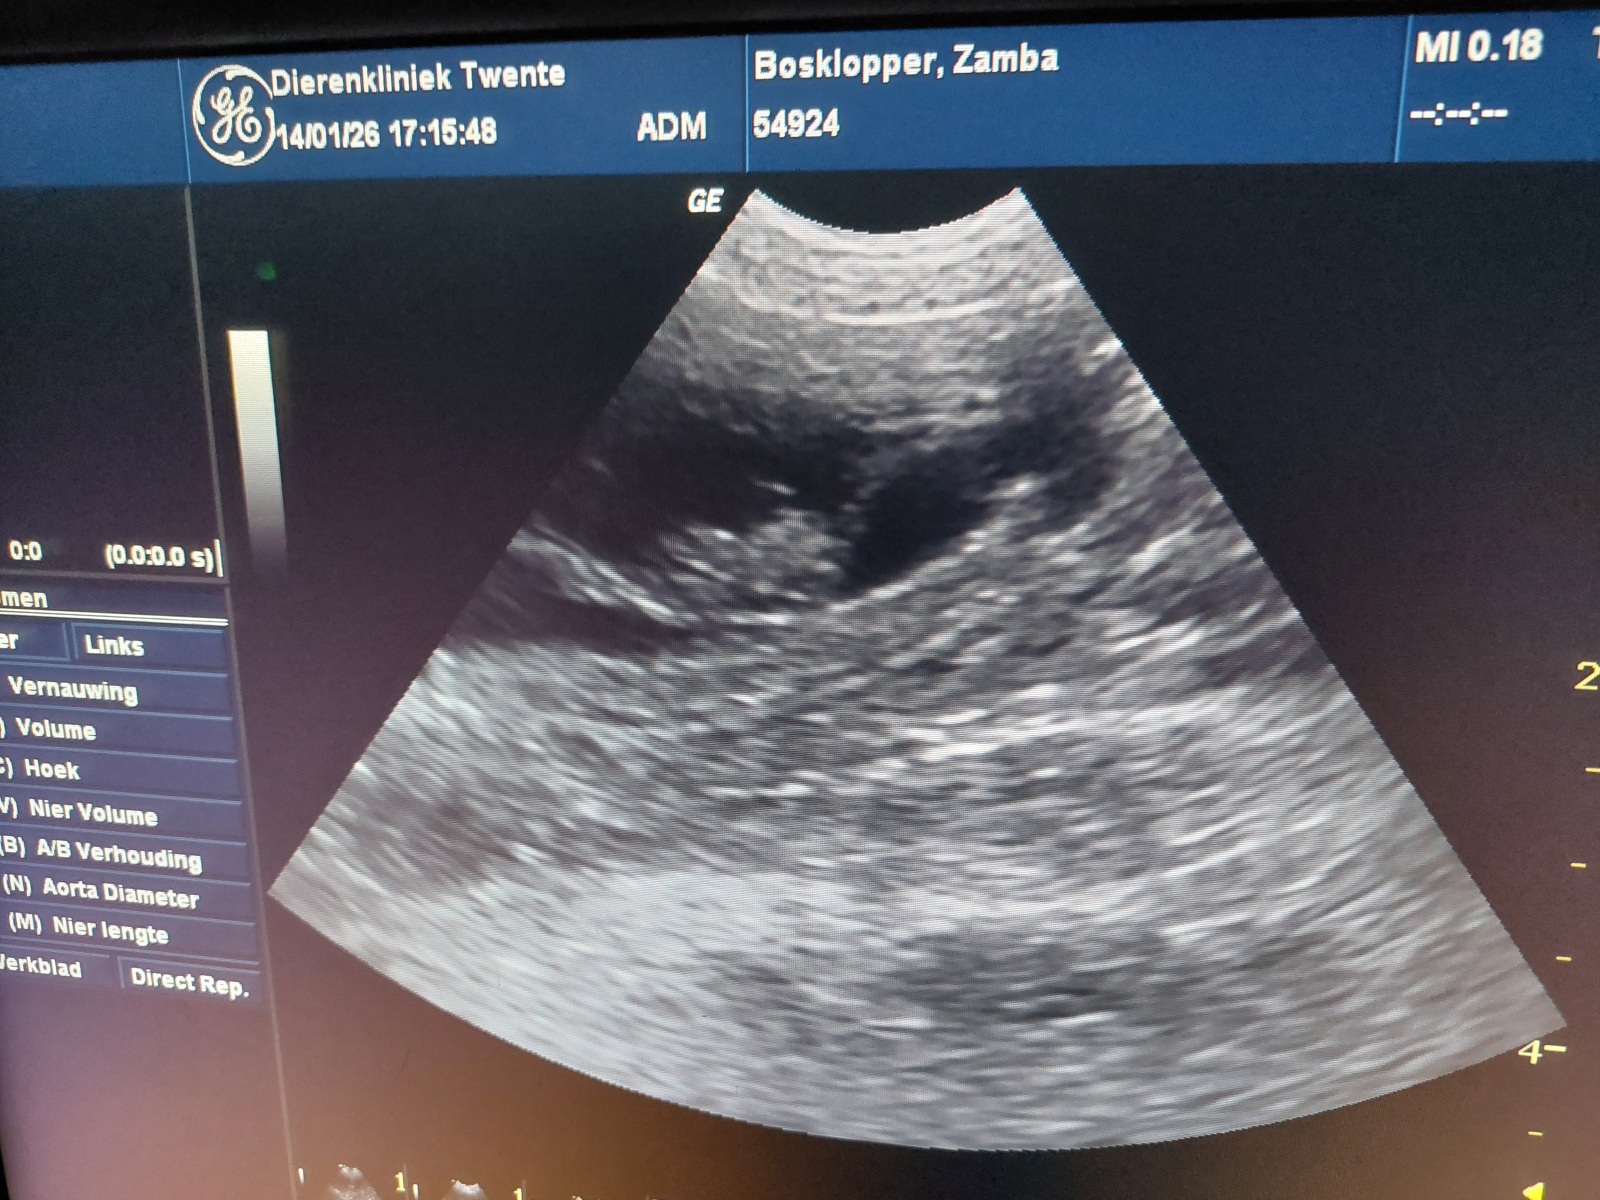

Op 14 januari 2026 is bij Dierenkliniek Twente in Enschede een echo gemaakt van Dazzling Flash Zamba. Tijdens dit onderzoek werd bevestigd dat zij dragend is. Alles ziet er op dit moment goed en gezond uit.

Op basis van de echo is de verwachting dat er waarschijnlijk vier pups onderweg zijn. Een echo blijft altijd een momentopname, maar de bevindingen geven een positief en geruststellend beeld van het verloop van de dracht tot nu toe.

Echo van de dracht bij Dazzling Flash Zamba, januari 2026Echo van de dracht bij Dazzling Flash Zamba, januari 2026